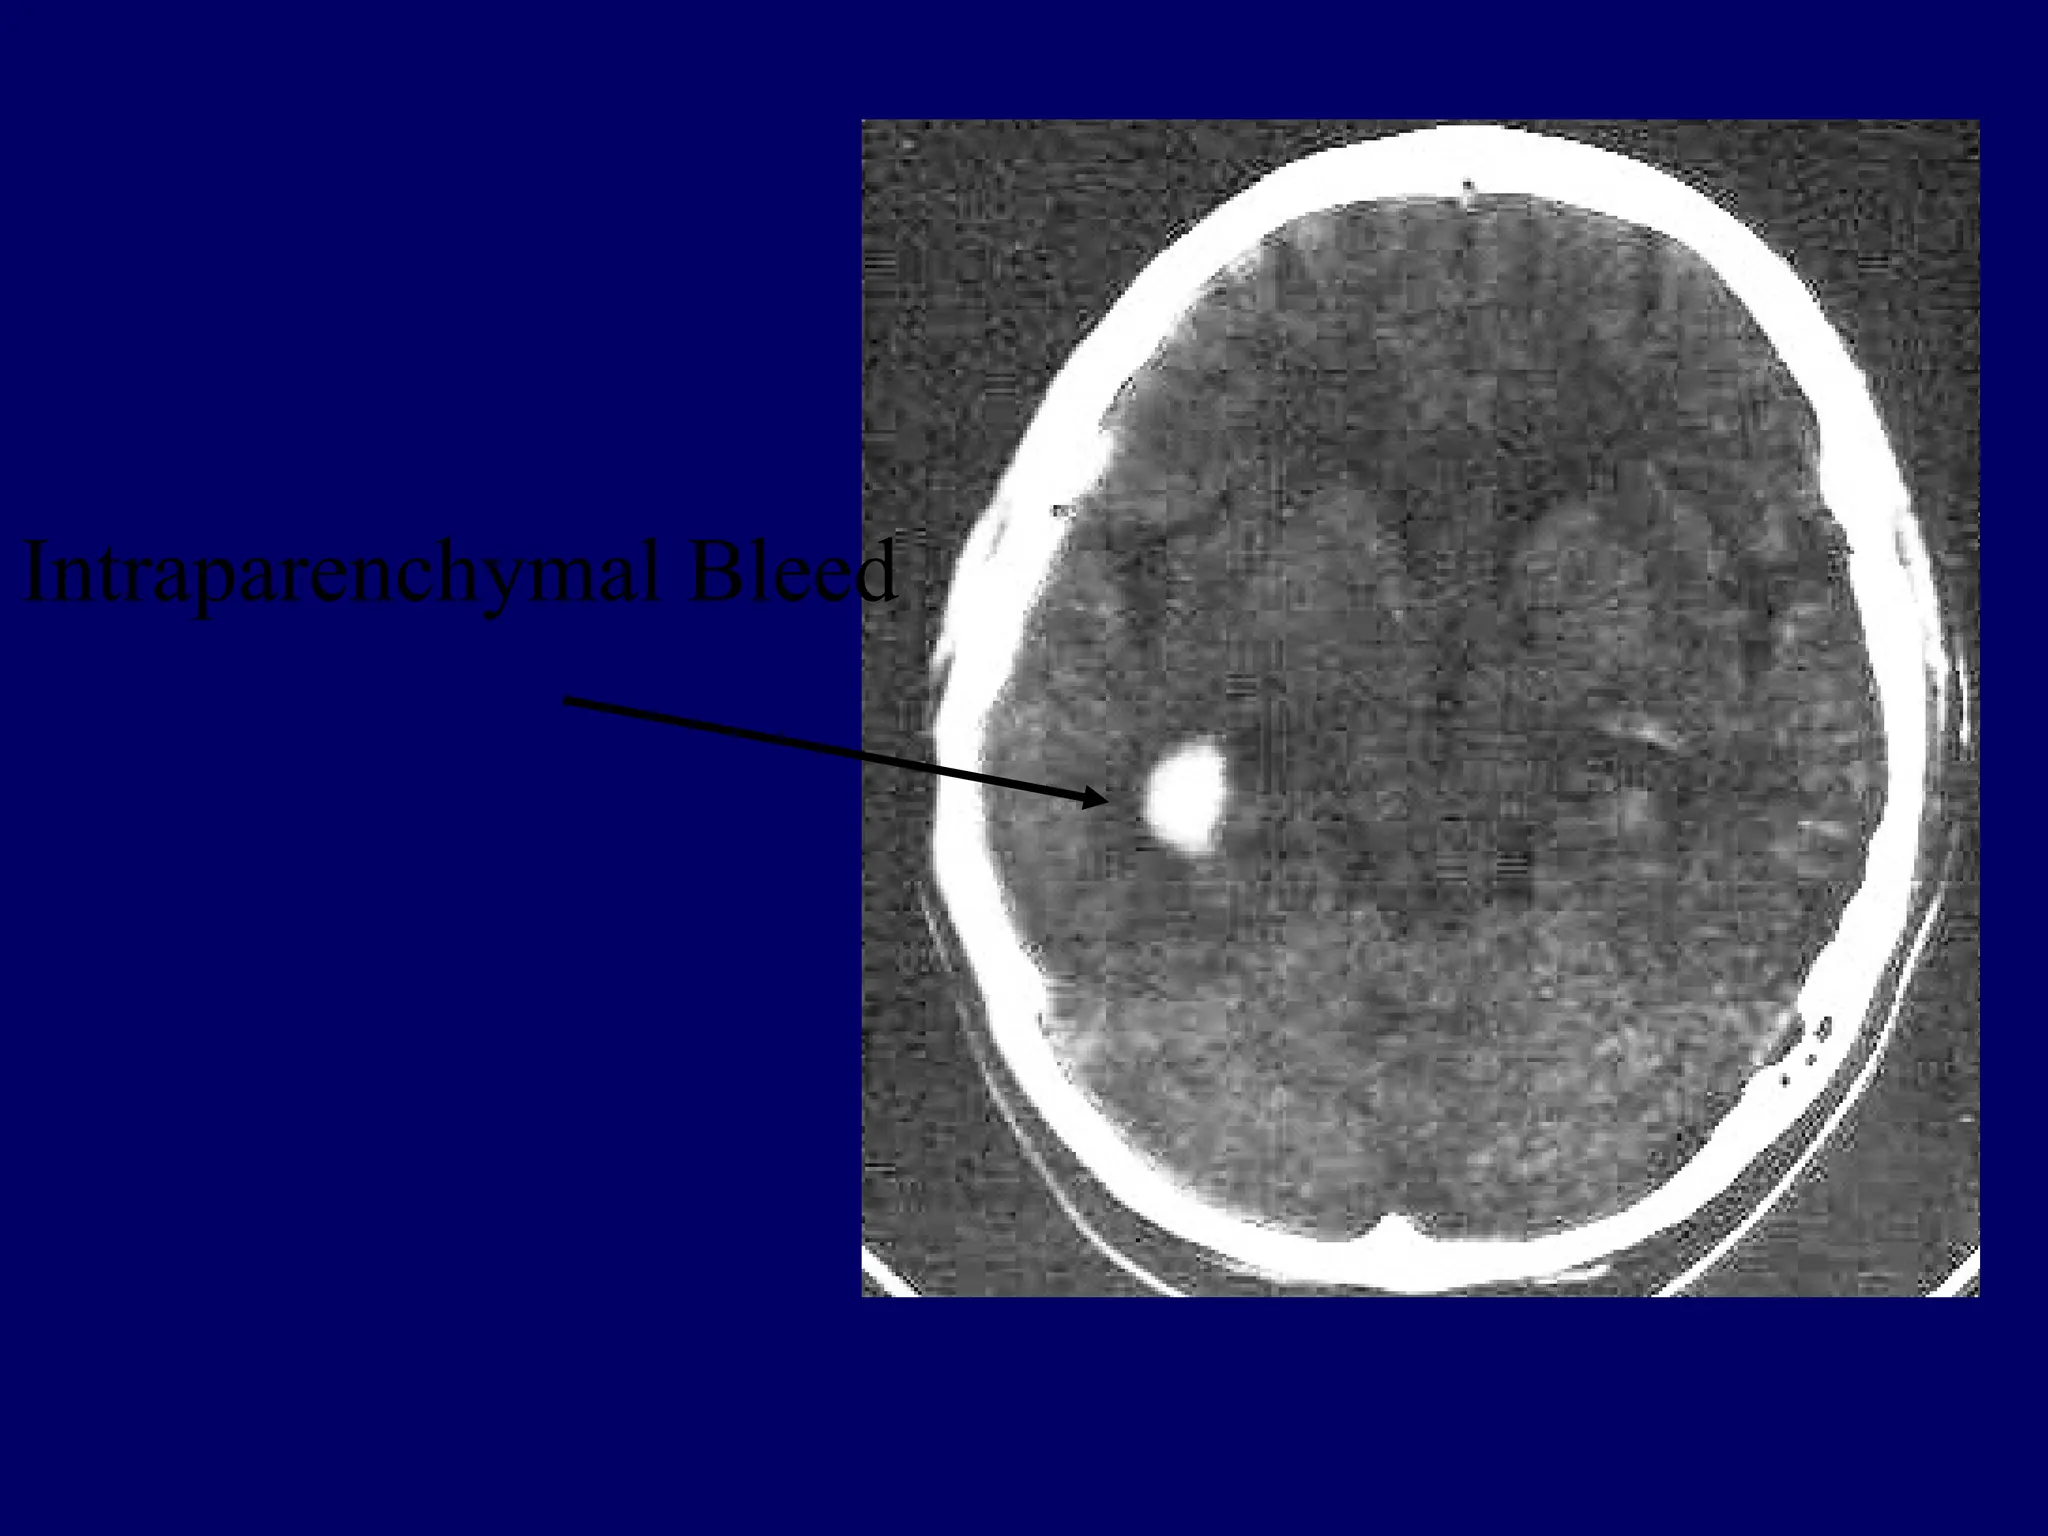

Intraparenchymal Bleed

Blood: Acute blood is white (60-80 HU) on

CT, due to the density of hemoglobin.

As hgb breaks down, the HU decrease (i.e.

• Hyperdensities (whiter), e.g

• extra-axial hematomas (SDH, EDH)

• ICB or contusion